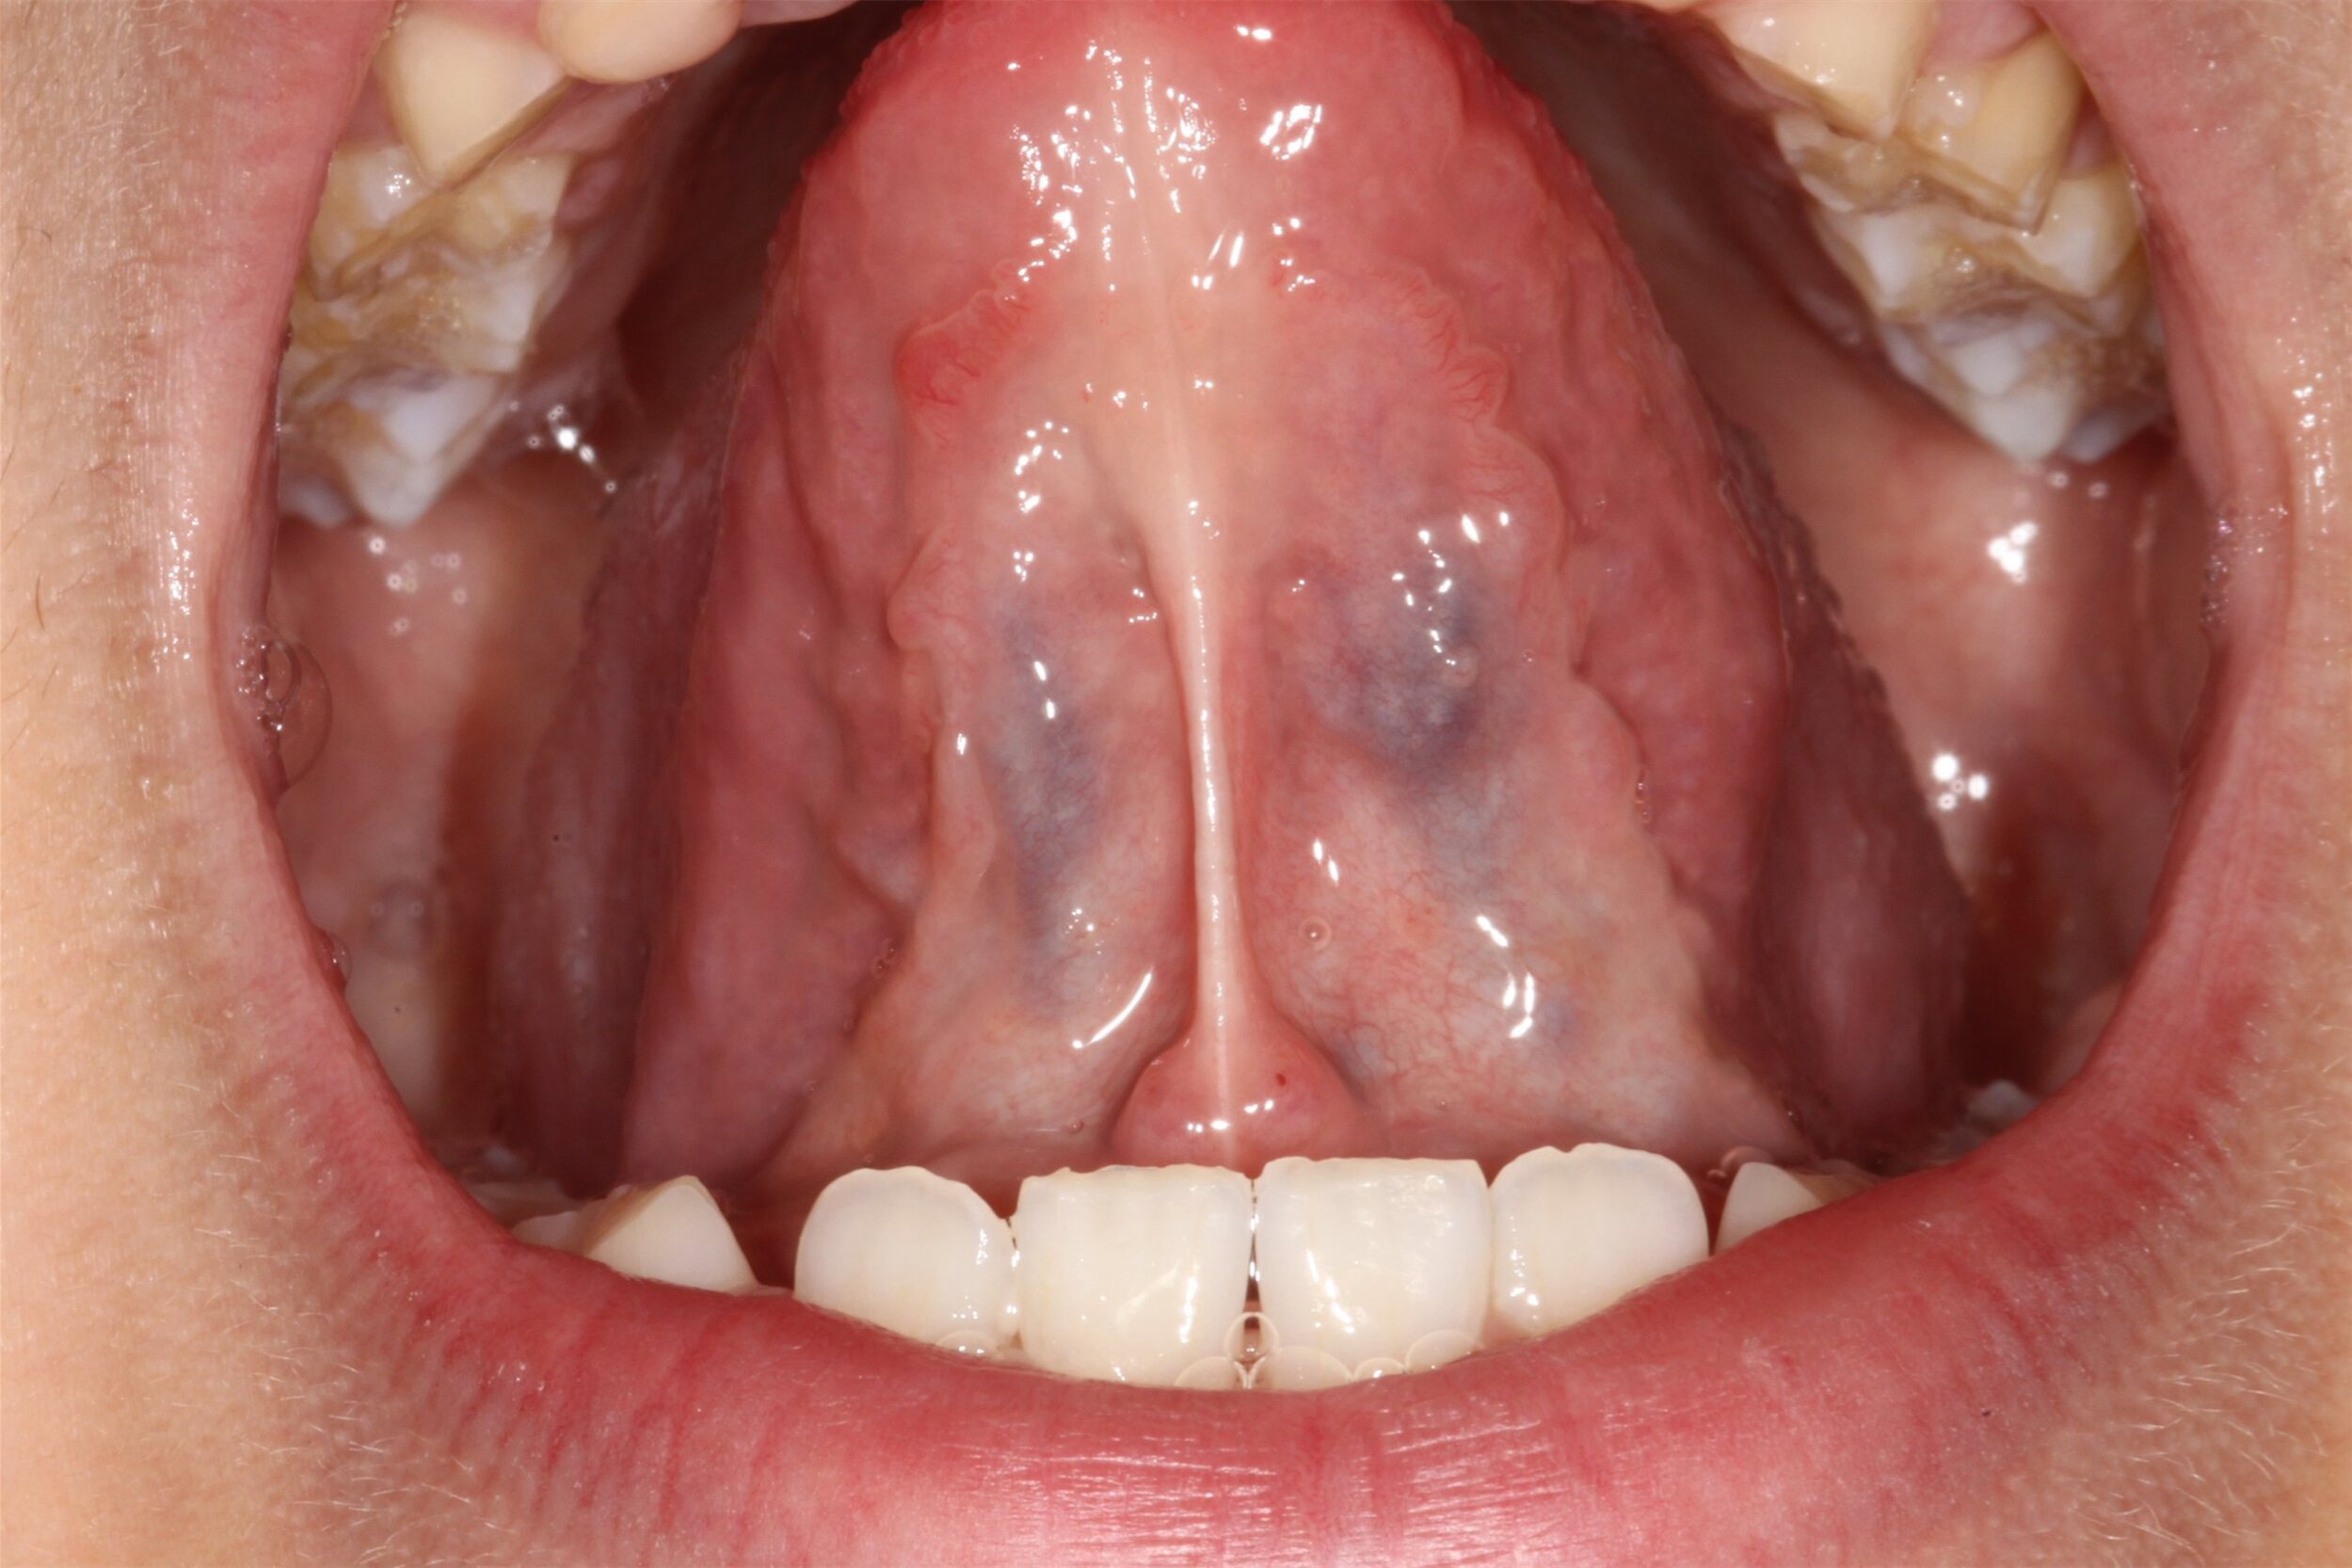

舌头下面的小肉芽可能是舌下肉阜、腺体导管开口、舌乳头状瘤或者尖锐湿疣等病症。

1.舌头下面有正常组织舌下肉阜,一般在舌系带两侧,像小肉芽一样。

2.舌下腺、颌下腺腺体的导管开口位于舌头下面,舌底的位置,一般是小肉上面有个小孔,左右对称分布,会有唾液流出。